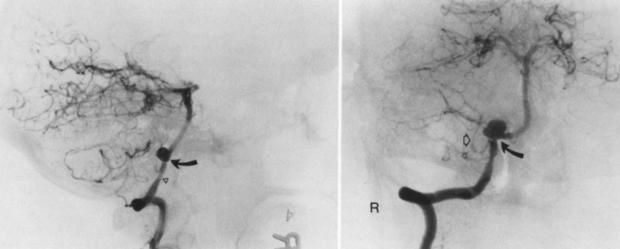

وقال استشاري ومدرس جراحة المخ والأعصاب إنه من الطبيعي أن يضل الدم للمخ عن طريق شرايين كبيرة ثم شرايين صغيرة ثم شعيرات دموية، ولكن في حالة حدوث ضيق في الشرايين الكبيرة، والشعيرات الدموية، يحدث قصور في الدورة الدموية للمخ، وهنا تحدث المشكلات الصحية.

وأضاف أنه في حالة ضيق الشرايين وعدم وصول الدم للمخ يلجأ المريض للجراحة، ويتم عمل قسطرة ودعامة كدعامات القلب بشكل دقيق للغاية.

من خلال فتح الجمجمة ووضع مشبك جراحي على تمدد الأوعية الدموية لغلقه، إذ يقوم الجراح بوضع مشبك جراحي من التيتانيوم على عنق تمدد الأوعية الدموية لإيقاف تدفق الدم، ما يمنع أي نزيف في المستقبل قد ينتج عن تمدد الأوعية الدموية.

حيث يتم قطع الشريان بأكمله الذي يأتي منه تمدد الأوعية الدموية، ومن ثم القيام بعلاج الوعاء الدموي الصغير بالشريان لإعادة توجيه تدفق الدم حول الجزء المقطوع وتجاوز تمدد الأوعية الدموية.

القسطرة والدعامة:

من خلال تركيب وحقنها بمادة للعلاج.